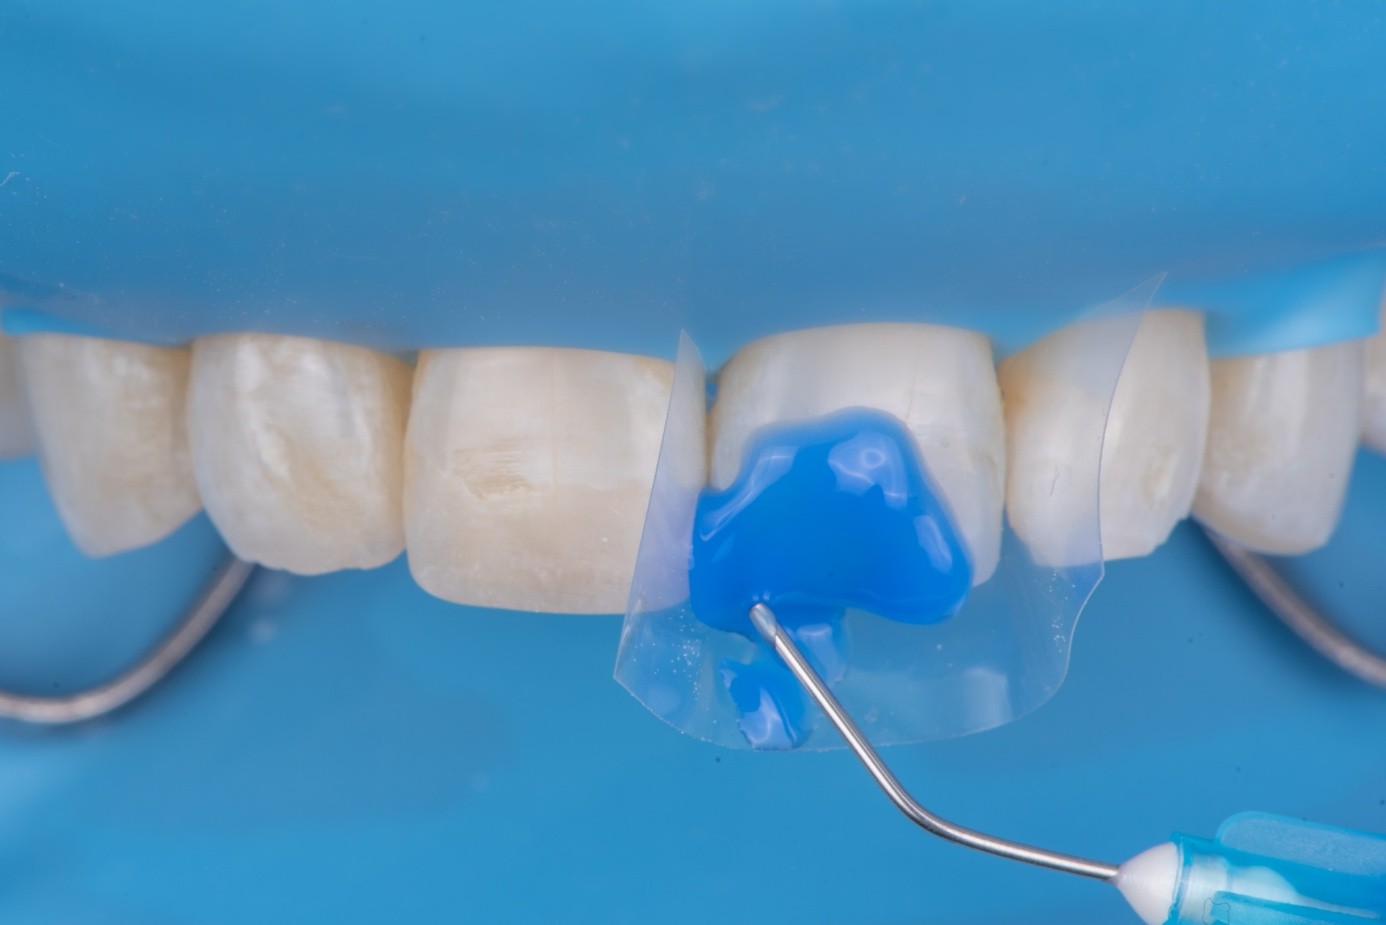

After achieving rubber dam isolation, the fractured composite segment was first air-abraded with aluminum oxide particles to clean and roughen the surface. It was then etched with phosphoric acid for 60 seconds, rinsed, dried, and treated with silane to enhance chemical adhesion (Figure 18 through Figure 20).8,9

The tooth surface was similarly air-abraded to remove biofilm and aged resin remnants, then selectively etched with phosphoric acid. Silane was applied intraorally to the exposed composite surface to promote bonding between the old and new composite layers.10 Following this, a universal bonding agent was applied to both the tooth surface and the fractured composite segment (Figure 21 through Figure 24).

(21.) Intraoral view after rubber dam isolation, showing prepared surfaces: both sandblasted and etched, with silanization applied only to the composite surface, ready for reattachment.

Figure 21

(22.) Intraoral view after rubber dam isolation, showing prepared surfaces: both sandblasted and etched, with silanization applied only to the composite surface, ready for reattachment.

Figure 22

(23.) Intraoral view after rubber dam isolation, showing prepared surfaces: both sandblasted and etched, with silanization applied only to the composite surface, ready for reattachment.

Figure 23

(24.) Intraoral view after rubber dam isolation, showing prepared surfaces: both sandblasted and etched, with silanization applied only to the composite surface, ready for reattachment.